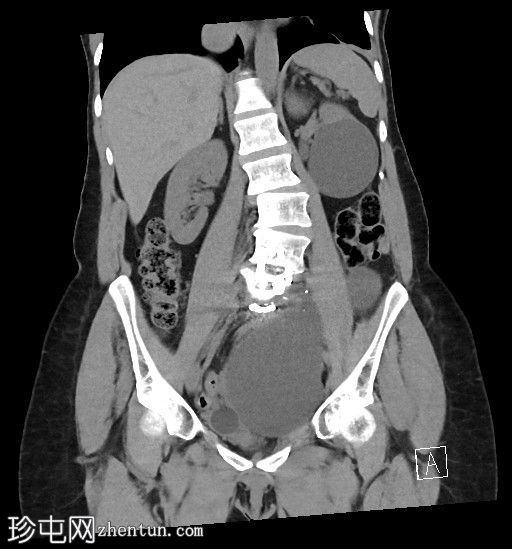

3.jpg

矢状位

平扫

左侧腹膜后可见一巨大囊性肿块,位于左侧腰大肌内侧,紧邻多个手术夹(ALIF手术所用),这些手术夹紧贴囊性肿块后壁。

膀胱已行引流管减压,并被囊性肿块向右侧推移。

子宫和左侧附件在囊性肿块前方保持正常的脂肪间隙,因此附件囊性病变的可能性较小。

左侧输尿管难以辨认,因为它位于囊性肿块下缘后方。

左侧腹膜后巨大囊性病变,符合术后淋巴囊肿。鉴别诊断包括血清肿、尿瘤和脑脊液积聚,但脑脊液积聚的可能性较小。